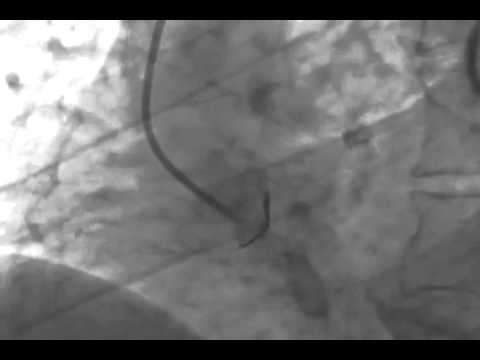

Video 7.9

Video 7.9: Engaging the LCA with the Multipurpose Catheter RAO projection